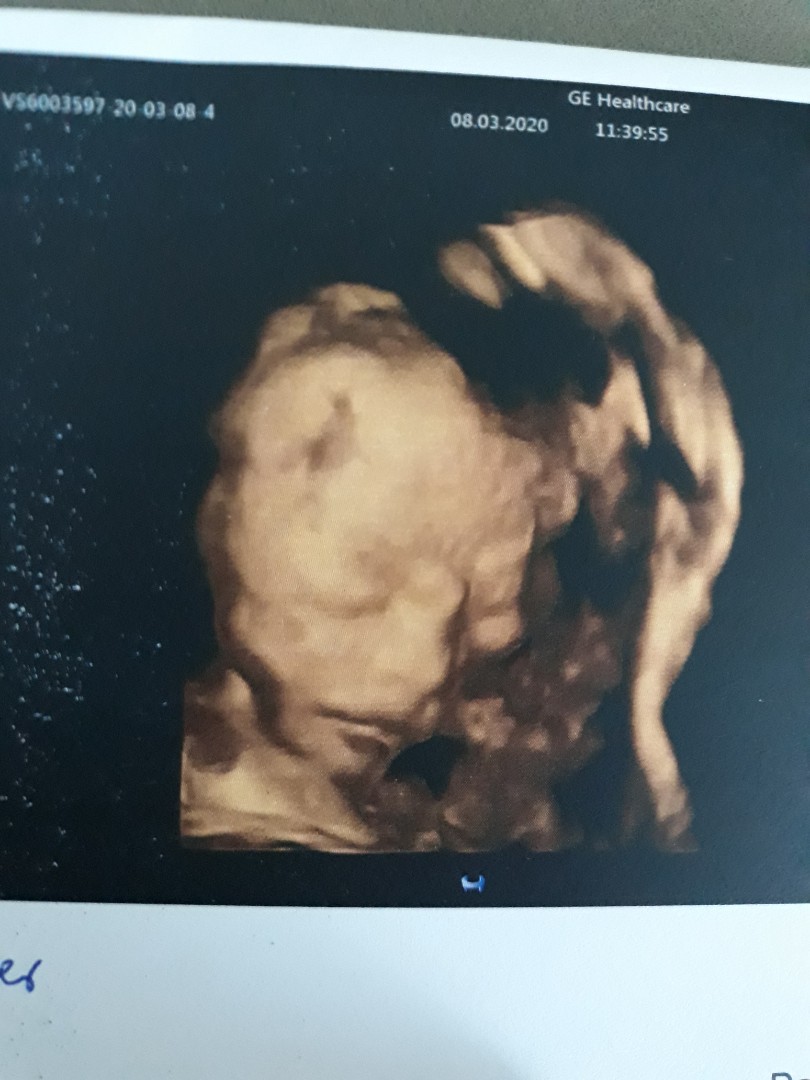

27wค่ะ